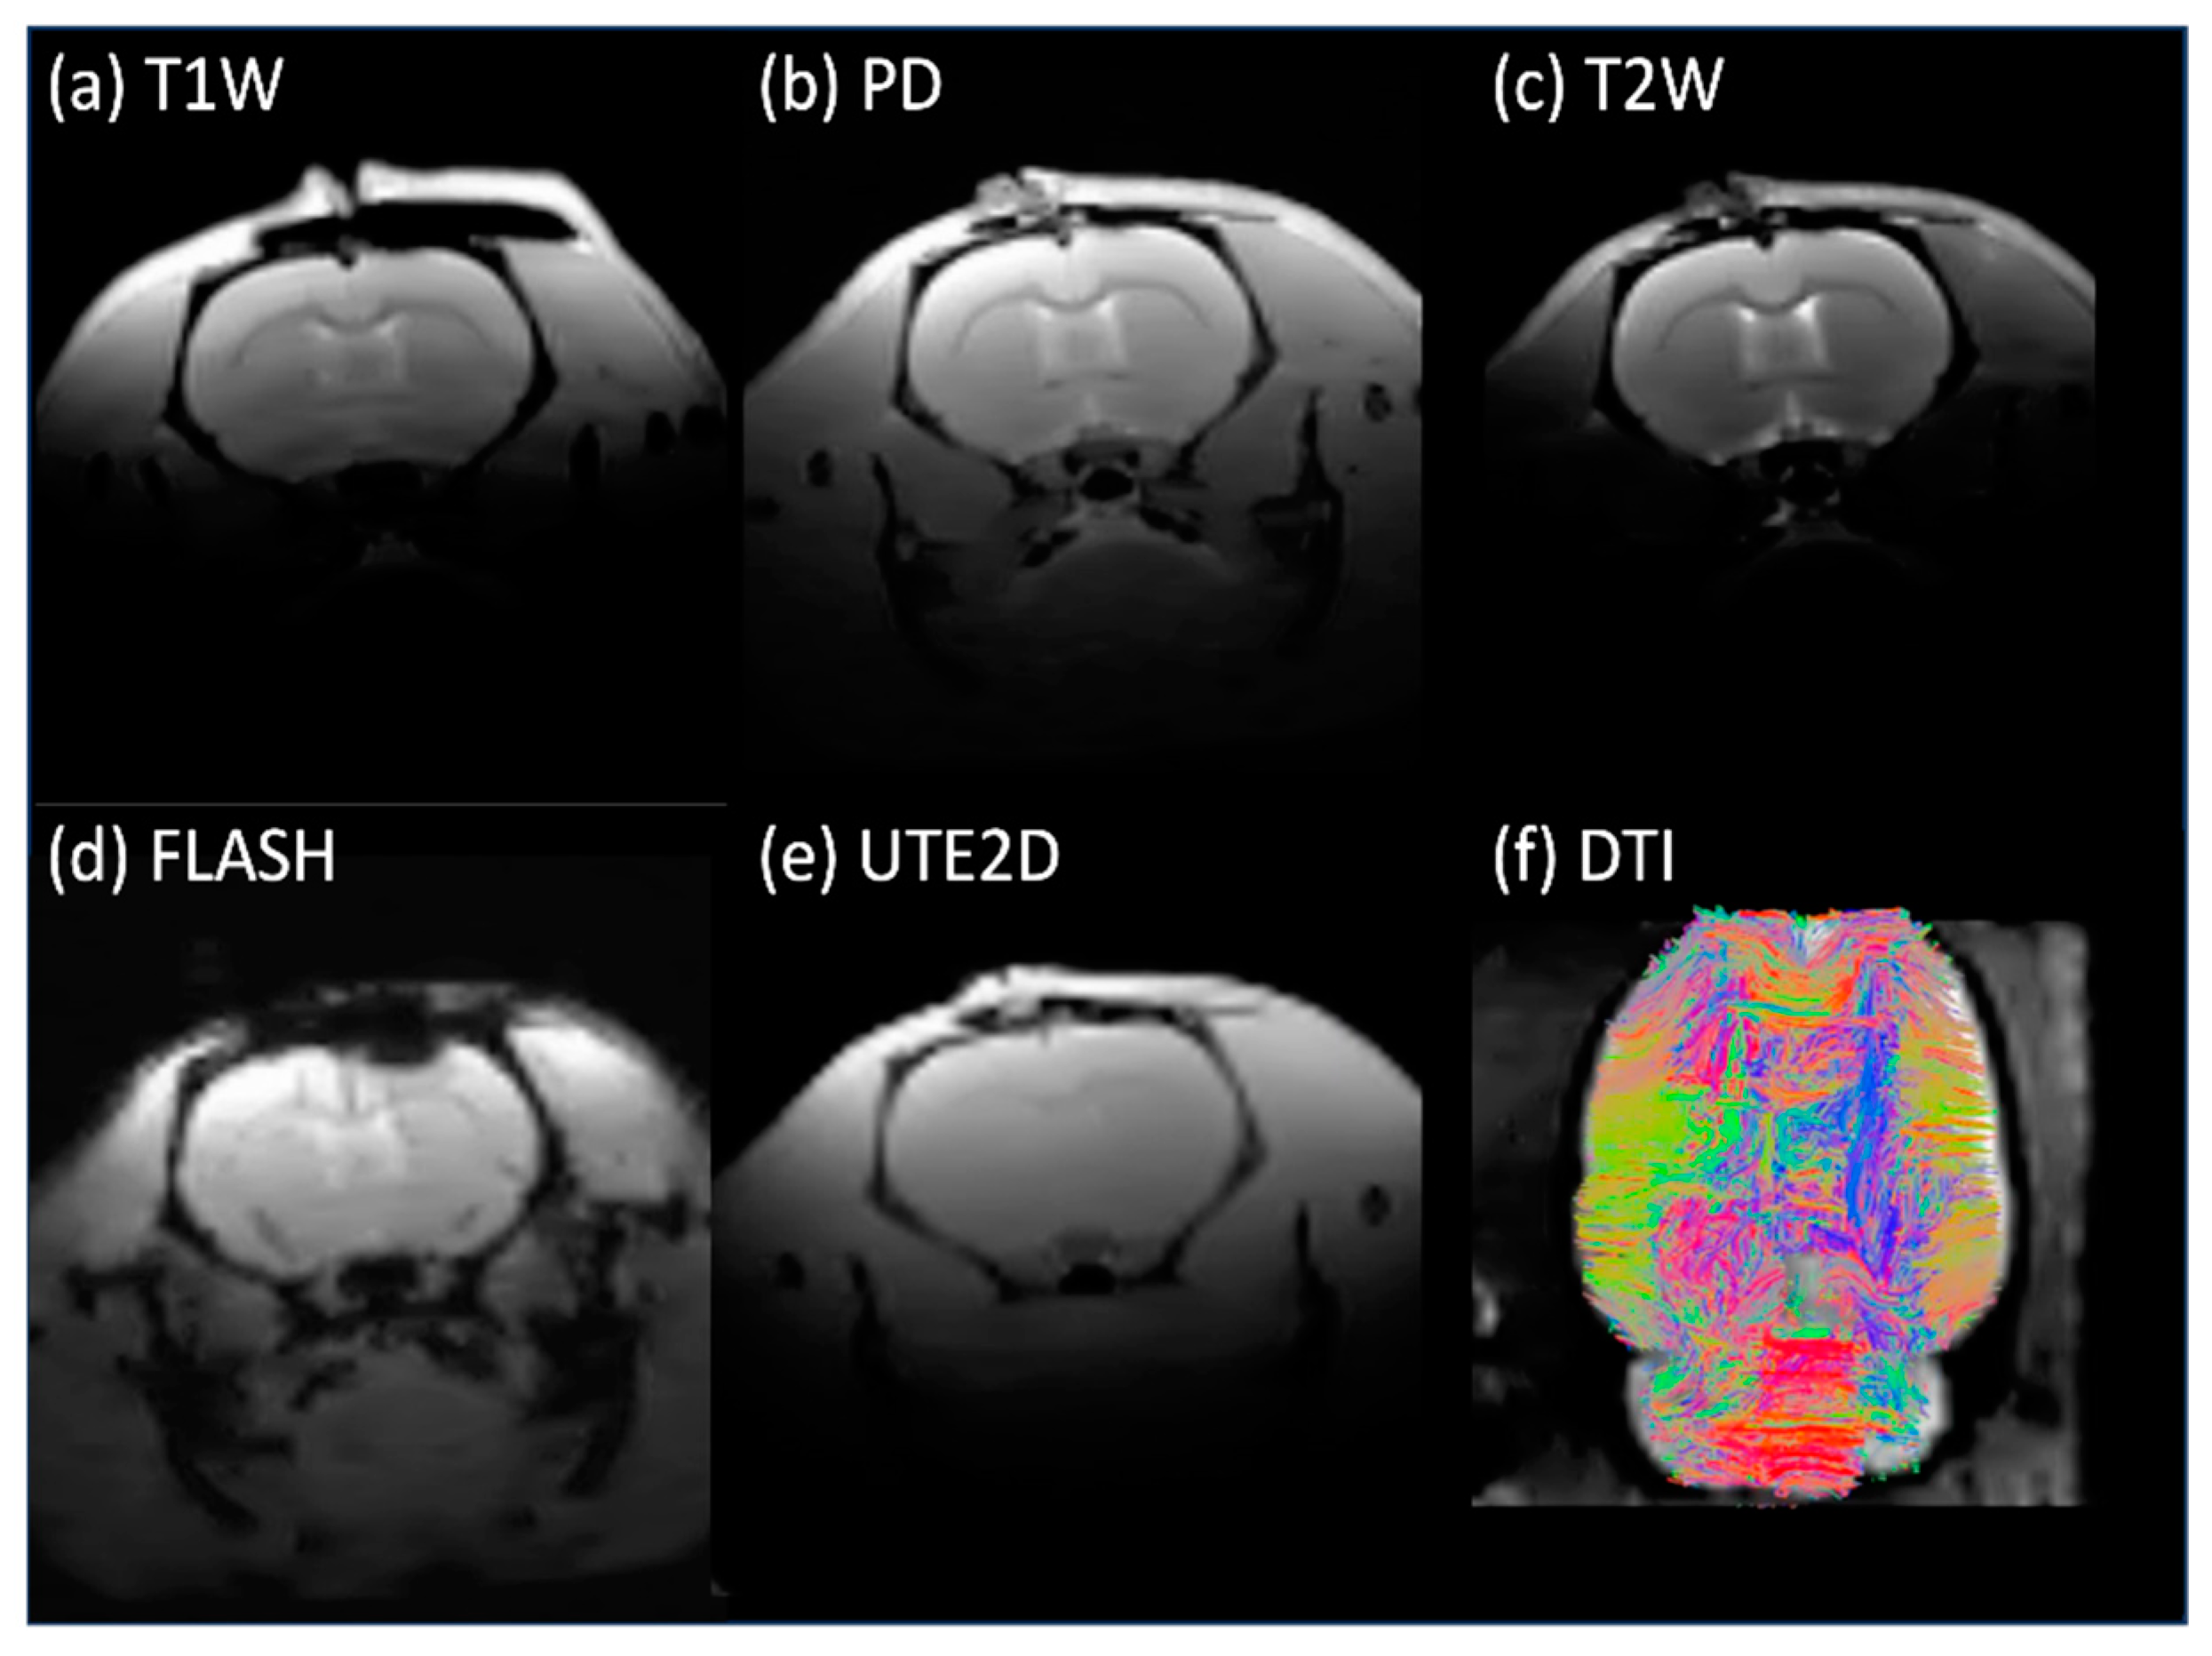

3.2. In Vivo Studies

| FOV (mm × mm) | Dimension | Resolution (mm × mm) | TR (ms) | TE (ms) | Slices | |

|---|---|---|---|---|---|---|

| Proton Density (PD) | 35 × 35 | 128 × 128 | 0.273 × 0.273 | 2192 | 8/52 | 22 |

| T2-Weighted (T2W) | 35 × 35 | 128 × 128 | 0.273 × 0.273 | 2192 | 8/52 | 22 |

| T1-Weighted TSE | 35 × 35 | 128 × 128 | 0.273 × 0.273 | 1500 | 7.5 | 22 |

| FLASH | 35 × 35 | 128 × 128 | 0.273 × 0.273 | 326 | 7.5 | 22 |

| UTE | 35 × 35 | 128 × 128 | 0.273 × 0.273 | 30 | 0.457 | 22 |

| DTI | 35 × 35 | 96 × 96 | 0.36 × 0.36 | 1416 | 23.9 | 44 |

| fMRI | 35 × 35 | 92 × 92 | 0.38 × 0.38 | 500 | 12.11 | 18 |